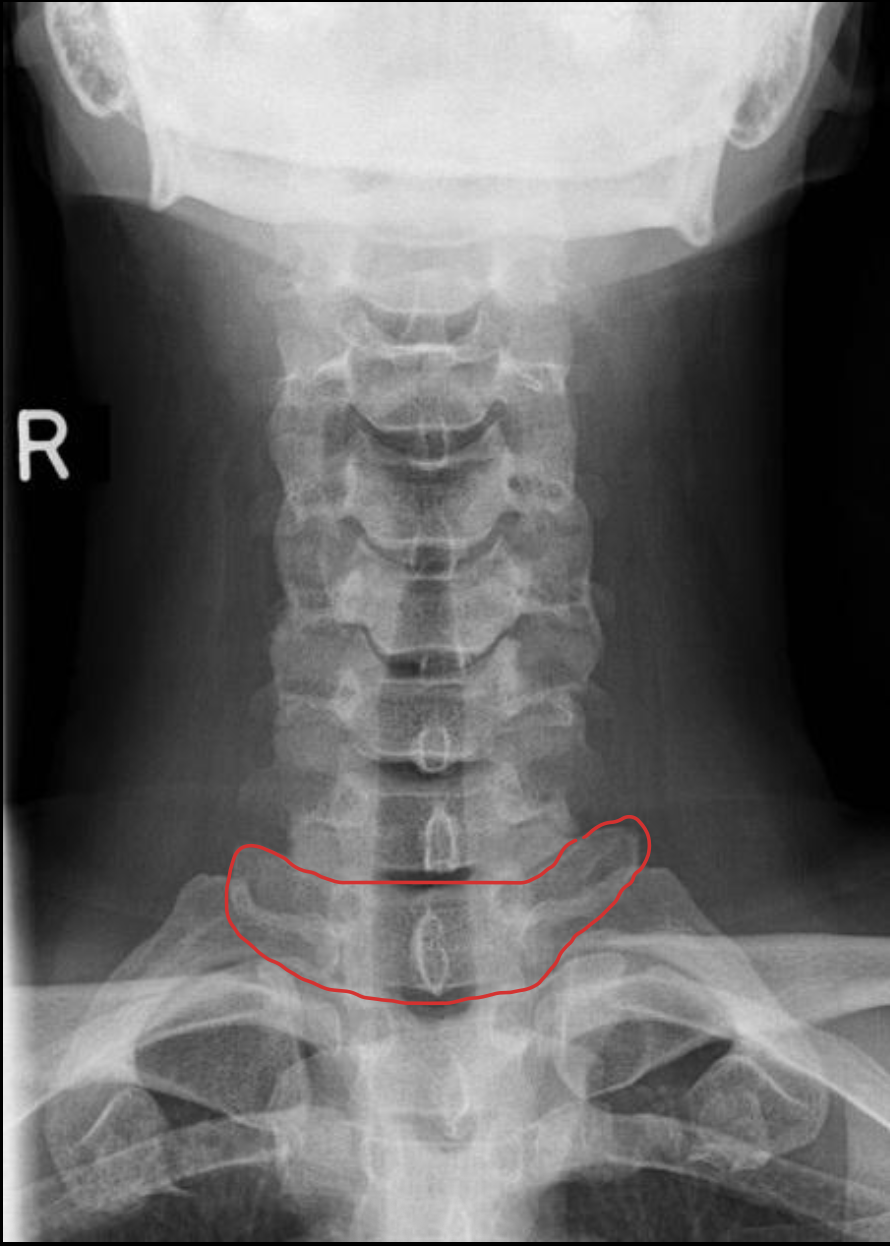

钩突

Uncinate process

关节柱 / 侧块

Articular pillars

棘突

Spinous process

椎间隙(Intervertebral Disc space)

IVD space

C7

T1

1st rib